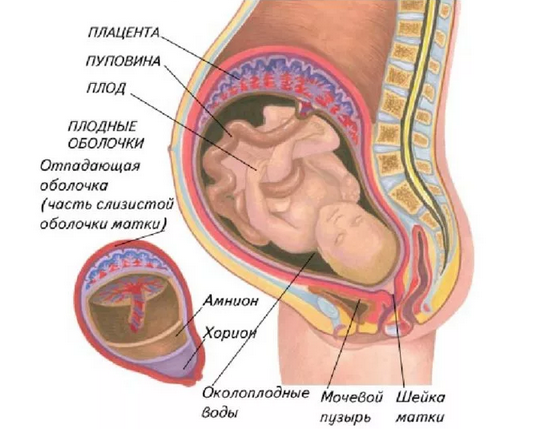

Околоплодный пузырь и плацента: структура и функции